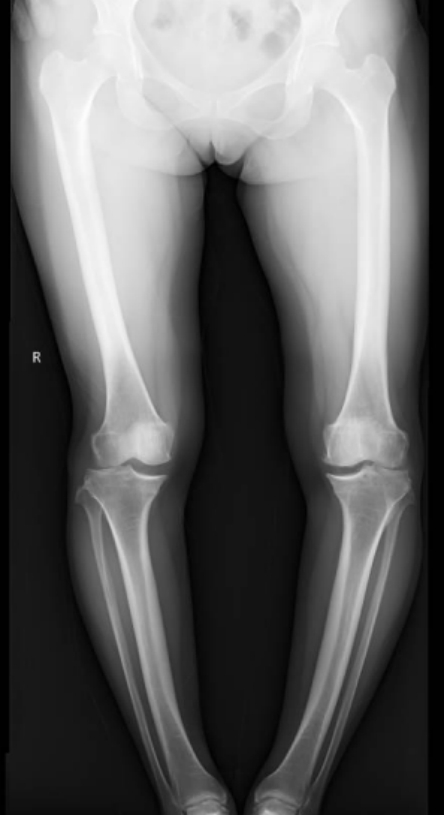

李彬在详细了解了董阿姨的病史、进行了全面的体格检查和相关的辅助检查后,组织科室进行了深入的讨论。最终的“答案”是——双膝骨性关节炎、双膝关节畸形、骨质疏松以及双膝半月板损伤。

面对这样复杂且严重的病情,李彬并没有退缩。他深知,对于董阿姨来说,这不仅仅是一次手术,更是一次重生的机会。因此,他精心制定了手术方案:对双下肢胫骨近端、远端以及双侧腓骨远端进行截骨矫形,并进行植骨内固定。这样的手术方案,无疑是对医生技术的一次高难度挑战!

手术前 手术后